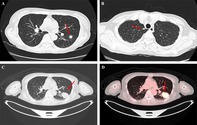

一名64岁的类风湿性关节炎和哮喘女性出现了快速生长和摄取18f -氟脱氧葡萄糖(FDG)的肺结节。尽管怀疑为恶性肿瘤,活检证实肺隐球菌病(PC)。无论FDG摄取情况如何,鉴别诊断时应考虑PC。

A 64-year-old woman with rheumatoid arthritis and asthma developed a rapid growth and uptake of 18F-fluorodeoxyglucose (FDG)-avid lung nodule. Despite suspicion of malignancy, the biopsy confirmed pulmonary cryptococcosis (PC). Regardless of FDG uptake, PC should be considered in the differential diagnosis.